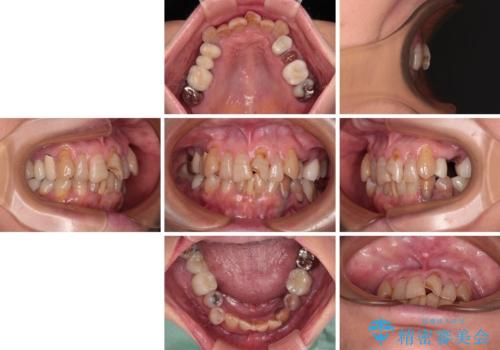

- 長年気にしていた捻れた前歯が欠けたとのことで来院された患者様です。

矯正治療に抵抗があったそうですが、前歯が欠けたことをきっかけに、矯正治療で歯列を整えた上で、セラミッククラウン治療を行う決心が付いたとのことでした。

デコボコが強いため、ブリッジや残根となっている部分のスペースを利用して歯列を整え、変色や欠けている歯をオールセラミッククラウンによる補綴治療を行うこととしました。